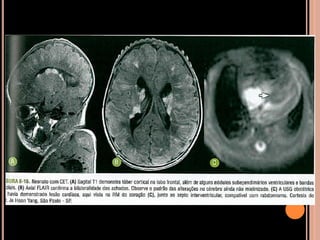

Achados de imagem

CET

Achados de imagem – Ressonância magnética

( V ) nódulo adjacente ao forame de Monro, com

calcificação parcial, impregnação pelo contraste

devem ser acompanhados anualmente;

( V ) os túberes são áreas de expansão e distorção

giral mais bem caracterizadas no FLAIR;